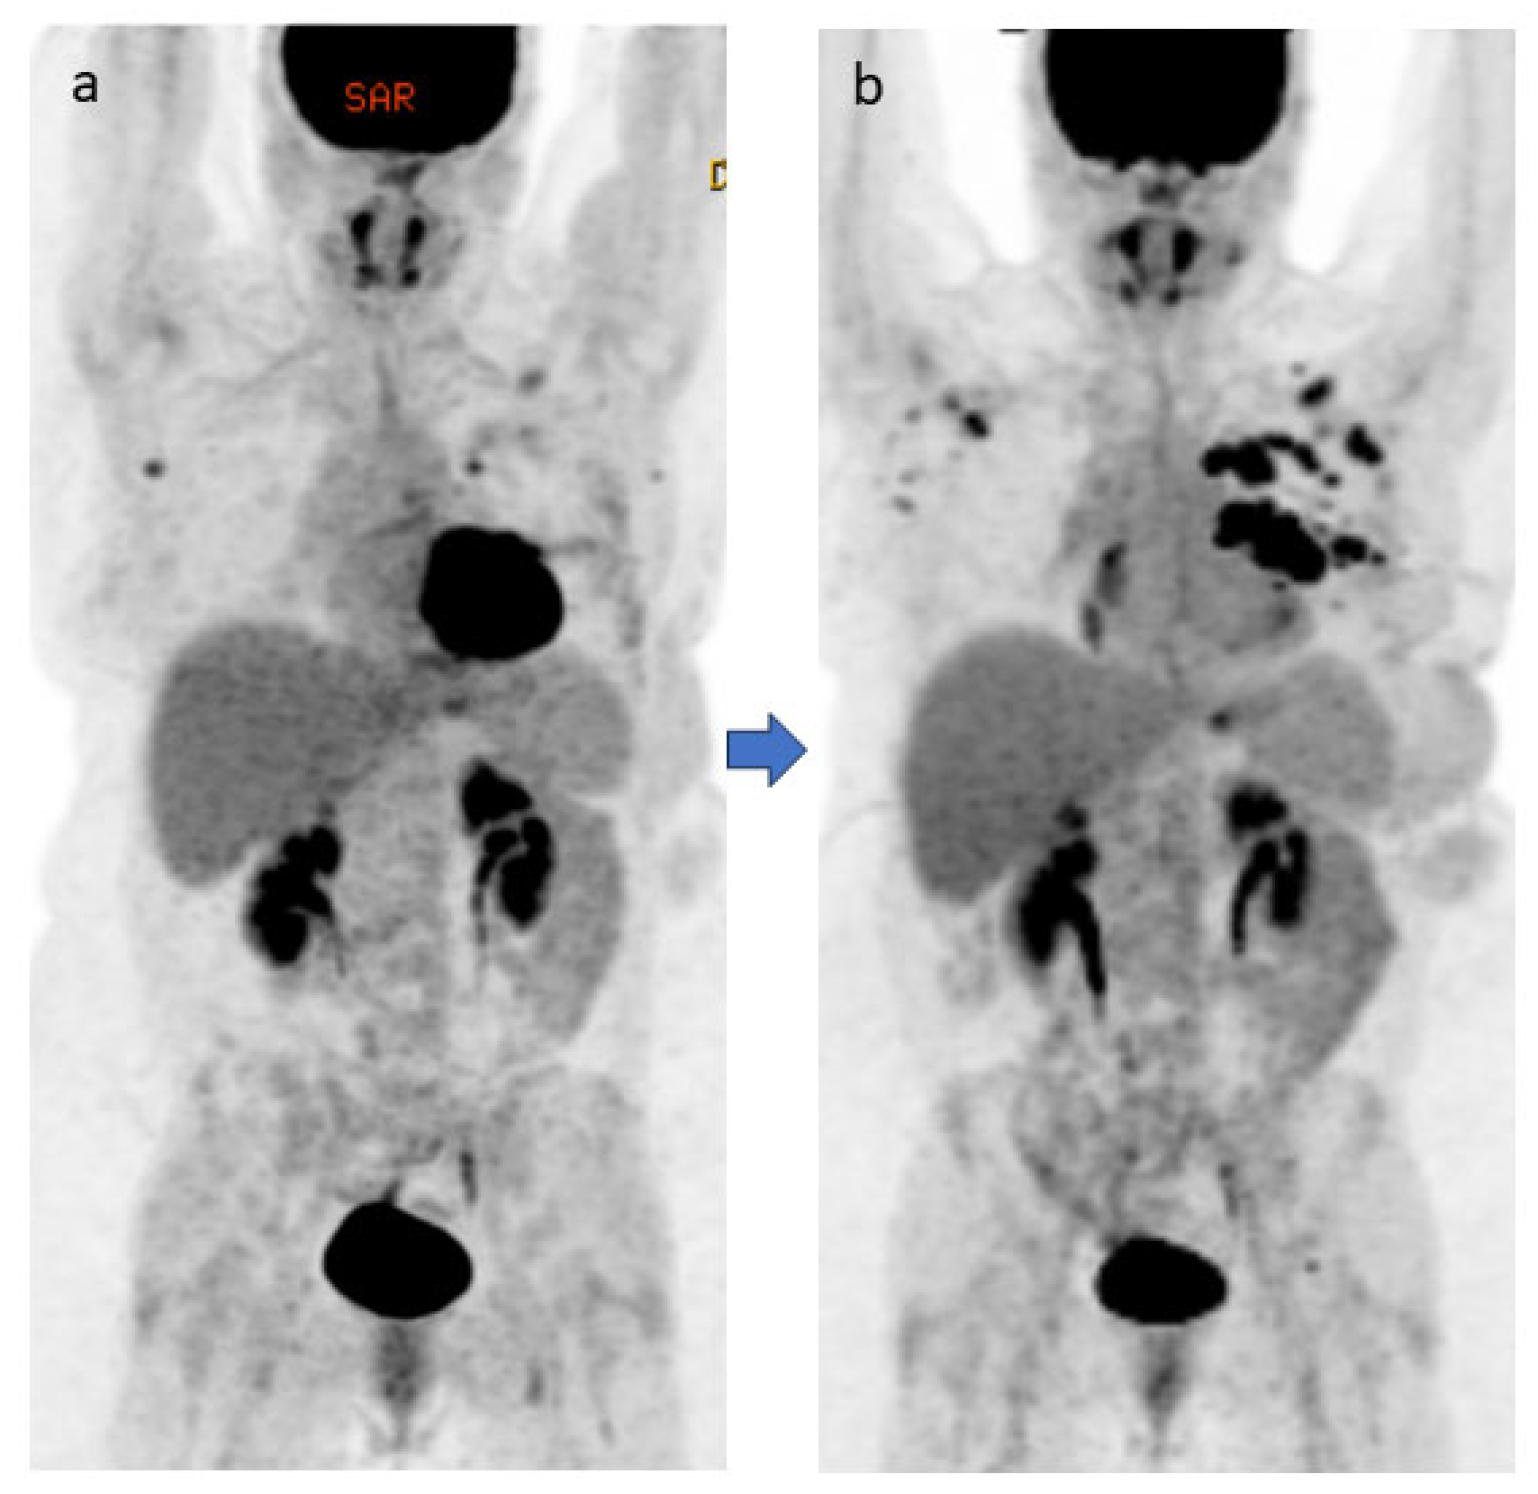

4.2. Case #2